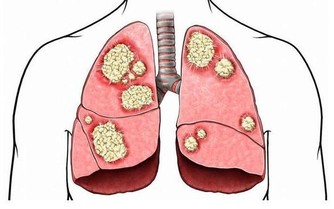

結果術後半年的一次體檢,發現她感染了艾滋病。經醫生分析,吳小姐半年前做紋眉時,感染艾滋的機率極大。工作室器具消毒不到位,很容易通過血液傳播各種疾病,其中就有艾滋病。

醫生提醒,梅毒、艾滋病等並不僅僅通過性傳播,紋身、打耳洞等有創美容,如果器具消毒不到位,也都可能傳播病毒。

紋身過程不衛生,不規範,會增大感染乙肝、艾滋病、細菌性紅眼病和沙眼、梅毒、結核病等的風險。